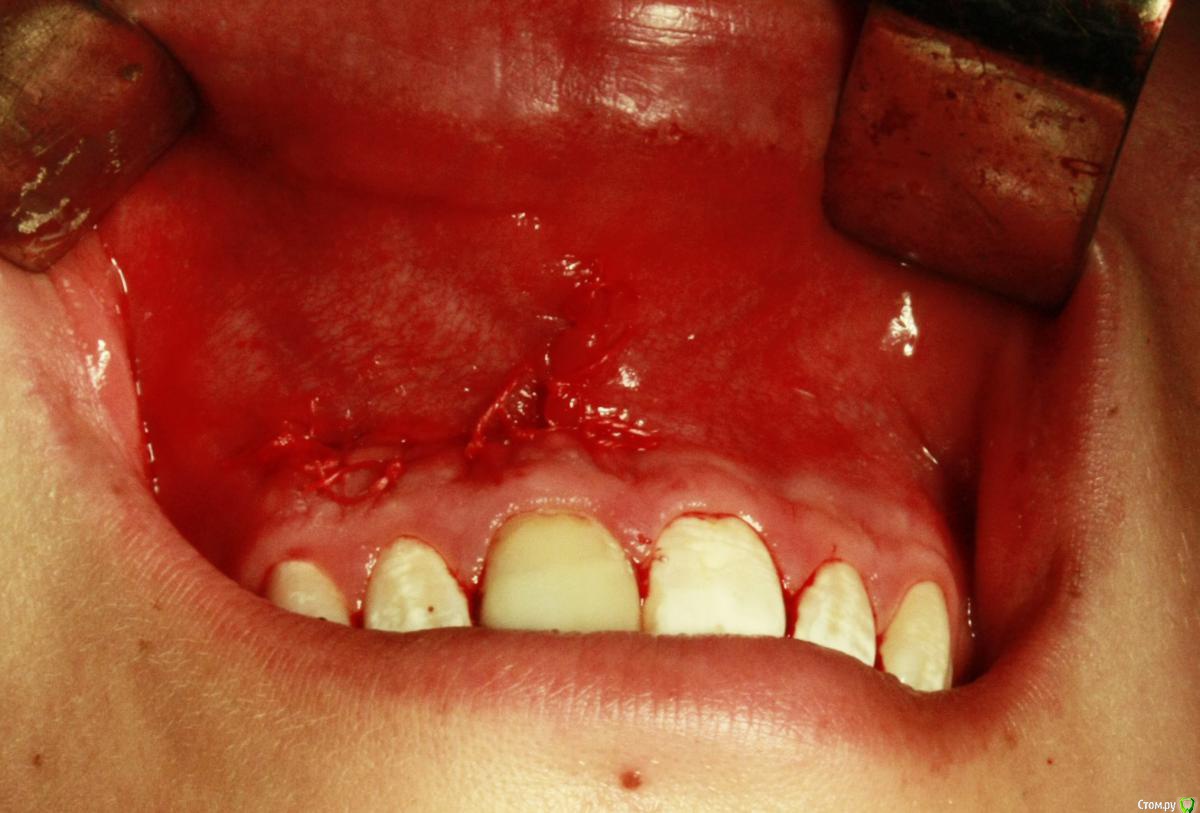

Дмитрий Б Опубликовано 6 августа, 2015 Поделиться Опубликовано 6 августа, 2015 Добрый день , уважаемые форумчане !Сегодня проводили резекцию , дефект закрывали ксено блоком (российским) + ауто .Есть ли по вашему мнению у блока шанс ?p.s. первый пост , прошу прощения за качество фото Ссылка на комментарий

Bier Опубликовано 6 августа, 2015 Поделиться Опубликовано 6 августа, 2015 Добрый день , уважаемые форумчане !Сегодня проводили резекцию , дефект закрывали ксено блоком (российским) + ауто .Есть ли по вашему мнению у блока шанс ?p.s. первый пост , прошу прощения за качество фото1.какова была цель резекции?2. Была ли ретроградная пломбировка?3. Почему такой странный дизайн разреза? P.S. Если все сделали правильно, блок прирастет во включенном дефекте конечно. 1 Ссылка на комментарий

M@estro Опубликовано 6 августа, 2015 Поделиться Опубликовано 6 августа, 2015 Будет рубец. Ретроградно обтурировали ? На мой взгляд - эта процедура в сотню раз важнее, чем аугментация в этой области. пятистеночный дефект, который ушит наглухо - там и сгусток сработает прекрасно, а вот рецидив , если не было ретроградной обтурации - это вопрос времени. 3 Ссылка на комментарий